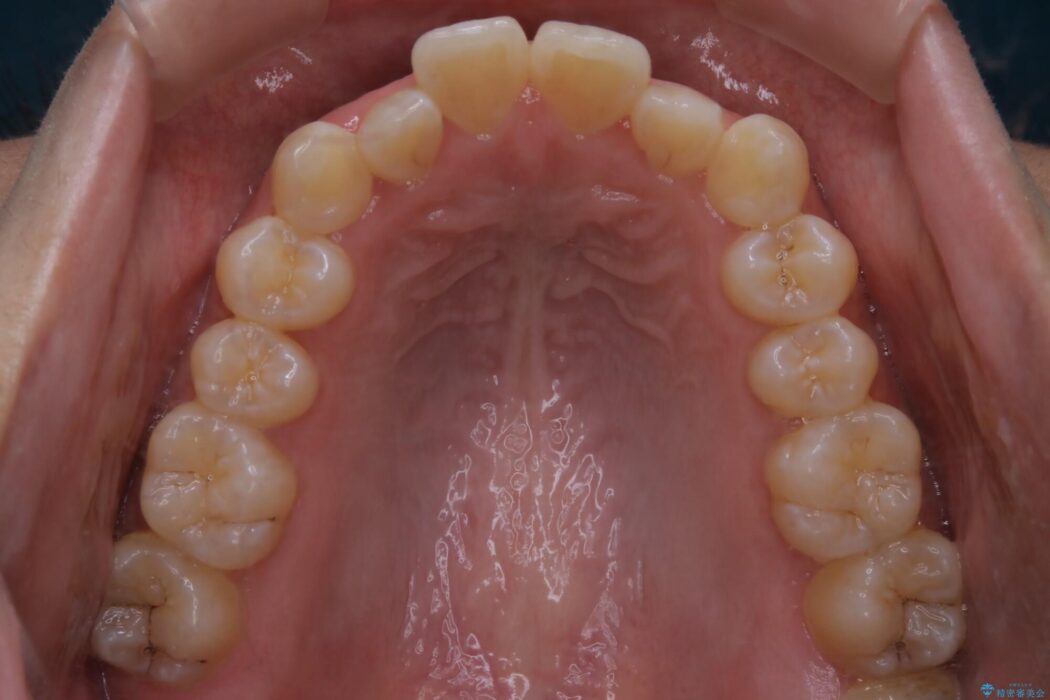

治療後について

反対咬合の歯も整ったアーチに収まり、きれいに仕上がりました。

今回のケースでは前歯部の軽い凹凸のみであったため部分矯正の適応範囲に該当していました。

適応例は限られますが、部分矯正は全体矯正と比べると矯正期間が短く、費用も安く済みます。